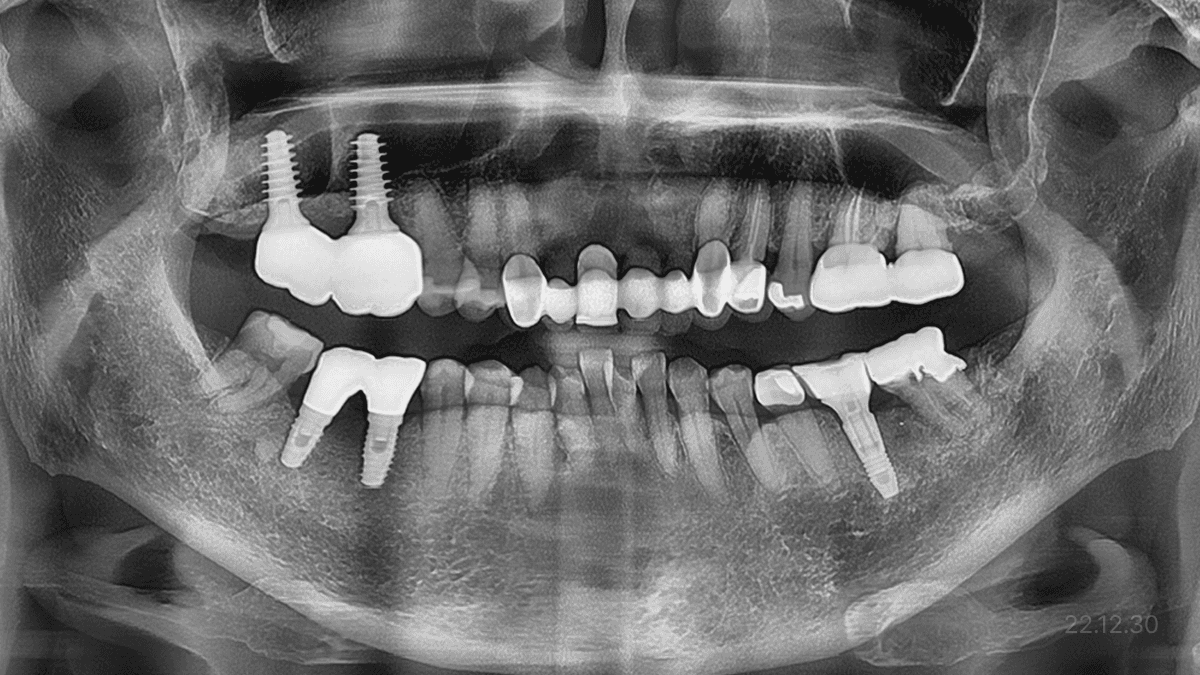

상악동 거상술 · 무절개 임플란트

상악동 거상술 ·

무절개 임플란트

상악동 격벽 · 매우 얇은 잔존뼈

*위 사진은 환자 본인 동의를 얻어 동일 조건에서 촬영 되었습니다. 모든 치료에는 부작용이 발생할 수가 있습니다.